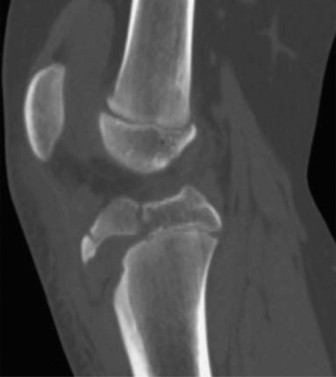

CASE 9 A 14-year-old boy is brought to the ER with complaints of right knee pa…